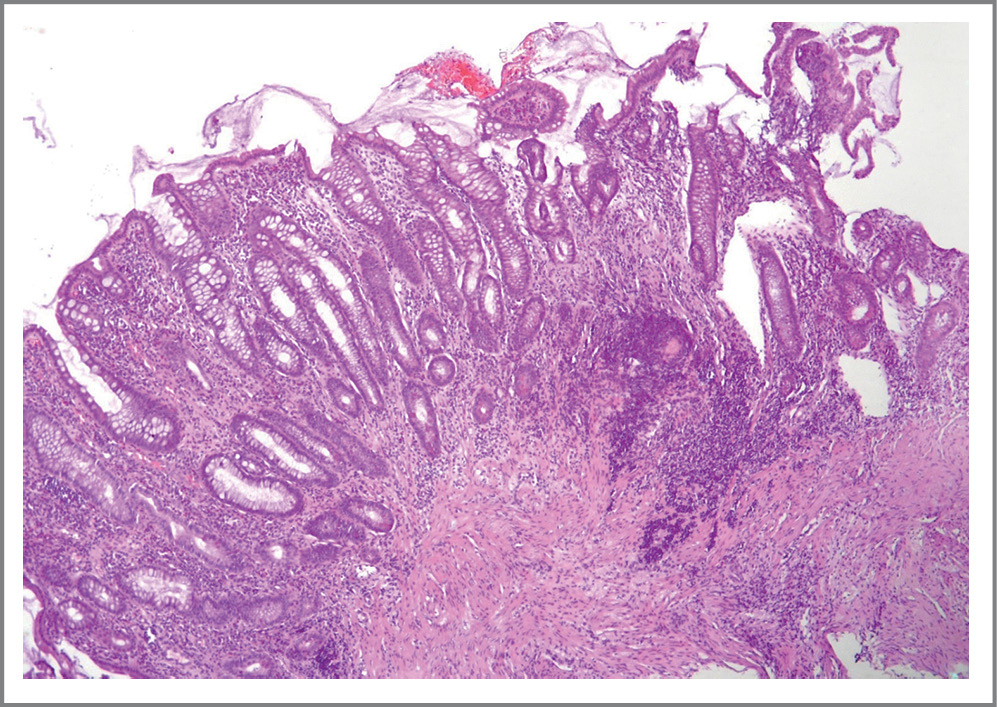

Даже на ранних стадиях язвенный колит характеризуется плотным, трансмукозным, богатым плазматическими клетками воспалением собственной пластинки с ремоделированием крипт (рис. 1).

Рис. 1. Ранние стадии язвенного колита. Деформация крипт, снижение количества бокаловидных клеток, участки базального плазмоцитоза. Клетки густого воспалительного инфильтрата не распространяются за пределы собственной пластинки слизистой оболочки. Окраска гематоксилином и эозином. ×120.

Fig. 1. Early stages of ulcerative colitis. Crypt deformation, decreased number of glass cells, basal plasmocytosis. Dense inflammatory infiltration cells do not spread beyond the mucous membrane’s own plate. Hematoxylin and eosin coloration. ×120.